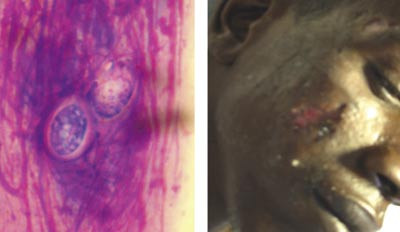

AIDS ble beskrevet som et syndrom i USA i 1981, og HIV-viruset ble identifisert som årsak i 1983. Høy dødelighet og dramatisk økning i forekomst førte til stor forskningsinnsats – og antakelig raskere kartlegging av årsak og patogenese og utvikling av diagnostikk og effektiv behandling enn på noe annet område i medisinen. Effektiv behandling har gjort sykdommen til en kronisk lidelse som krever kontinuerlig behandling og kontroll, men som pasienten kan leve med uten at levetiden blir vesentlig forkortet. Behandlingen er komplisert, og området har i praksis utviklet seg til en subspesialitet innenfor infeksjonsmedisin i mange land.

Resistensutvikling hos mikroorganismer har gjort at sykdommer vi trodde var under kontroll, på ny gir store problemer. Både malaria og tuberkulose øker kraftig, spesielt i utviklingsland. Vi har også fått en betydelig resistensutvikling hos pneumokokker, stafylokokker (MRSA) og ulike gramnegative stavbakterier. Disse problemene har vært så alvorlige at det er blitt diskutert om vi er kommet til slutten av den antibiotiske æra (4).

Det er økende forekomst og større utbredelse av mange tidligere kjente infeksjoner som følge av endrede egenskaper (gruppe A-streptokokker), sosioøkonomiske forhold, vaksinasjonssvikt (difteri, kikhoste, meslinger) og andre faktorer – hygienesvikt, økt reisevirksomhet og klimaendringer (kolera, denguefeber, gulfeber).